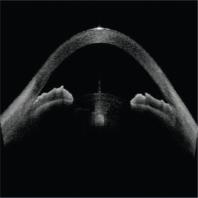

- eFig. 14-2 - Fermeture de l'angle en OCT

- eFig. 14-3 - UBM iris plateau

- eFig. 16-3 - Coupe d'OCT de segment antérieur de type Spectralis® :